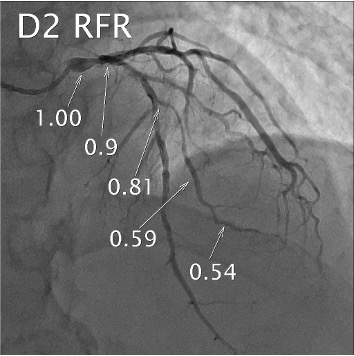

LAD FFR & Dx RFR